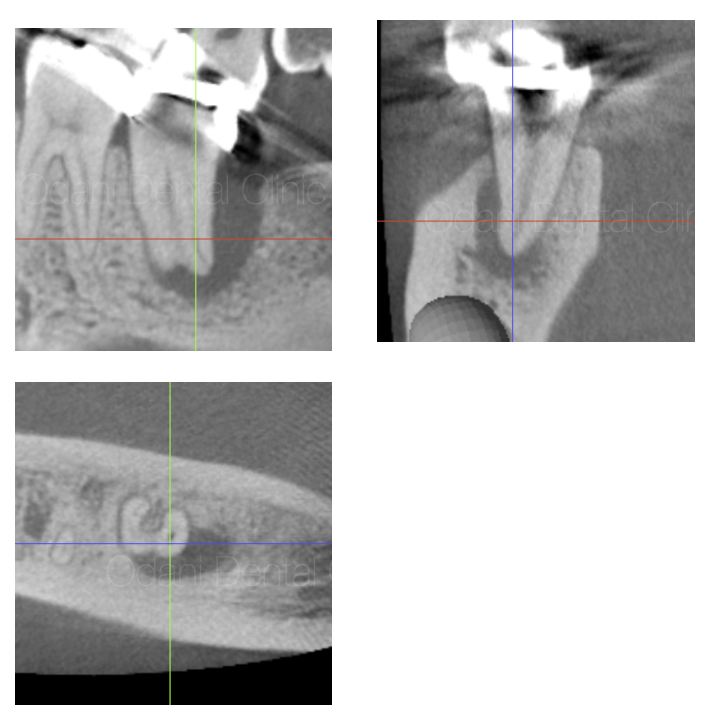

CT画像では、歯の根の周囲の骨が大きく吸収していることが確認でき、それに伴い歯ぐきの腫れや、歯周ポケットが10mm以上と深い状態になっていました。

歯の保存が困難となる可能性も高い状態で抜歯もよぎりましたが、根管内の細菌が原因(専門的病名としては歯内歯周複合病変)と診断し、相談の上で保存の可能性にかけて感染根管治療を行うこととなりました。

術後1年の評価にCT撮影を行いましたが、完全な治癒を認めることができました。